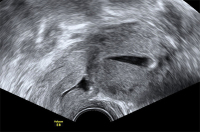

Tipps und Tricks im Gyn-Ultraschall: Die Sectionarbe am nichtschwangeren Uterus und in der Frühschwangerschaft

Journal für Gynäkologische Endokrinologie 2014; 8 (2) (Ausgabe für Österreich): 22-24 Journal für Gynäkologische Endokrinologie 2014; 8 (2) (Ausgabe für Schweiz): 24-26 Volltext (PDF) Abbildungen